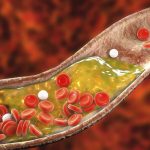

آرتروز زانو زمانی رخ میدهد که غضروفی که در مفصل نقش ضربهگیر را ایفا میکند، به مرور زمان فرسوده میشود و در نهایت انتهای استخوانها به یکدیگر ساییده میشوند.